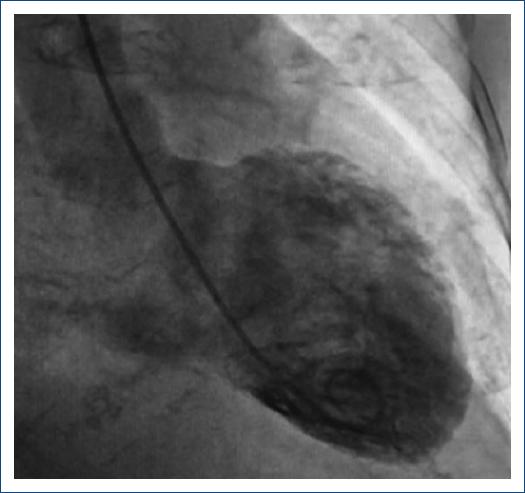

A 75-year-old female with a lymphoma record, diabetes mellitus 2, and hypertension, was hospitalized in another institution with a diagnosis of urosepsis; she required vasopressor treatment and a 3rd generation cephalosporin 2 weeks ago with a partial clinical improvement; but two weeks later she returned to the same hospital with dyspnea and peripheral edema. At the physical examination highlights general rales and peripheral edema, an electrocardiogram (ECG) showed sinus rhythm with ST-segment elevation in V2-V6, DI, and aVL. The troponin I level was 620 ng per liter on a high-sensitivity assay, and she was referred to our institute. Upon her arrival to the emergency department at our insistution, she had a Glasgow score of 10 points, respiratory distress and medium blood pressure <65 mmHg. The ECG persists with a ST-segment elevation in V2-V6, DI, and aVL (Fig. 1). The patient was intubated and required invasive mechanical ventilation, we started anti-ischemic treatment and vasopressor. In the context of ST-segment elevation myocardial infarction and cardiogenic shock, she was transferred to the cardiac catheterization laboratory, where it was reported the absence of injuries in the right coronary, circumflex, and anterior descending arteries (Fig. 2). With anterior and inferior akinesia, and apical dyskinesia, suggestive of Takotsubo cardiomyopathy (Fig. 3). After that, she was transferred to the coronary care unit where the diagnosis of cardiogenic shock was integrated. We iniated treatment with an inodilator (levosimendan) and inserted an intra-aortic balloon pump (IABP) as a ventricular-assistant device. A transthoracic echocardiogram was performed, reporting basal hypokinesia, apical akinesia. LVEF 12%, without a dynamic obstruction of the left ventricular outflow tract and a lung ultrasound with a B-profile. Urine and blood culture were negative; she presented a clinical improvement, so the vasopressor and inodilator were retired and started deflating the IABP. We performed another echocardiogram obtaining a LVEF 27%. As she presented clinical improvement as the days went by, we removed the ventricular assistant device. Unfortunately, in a sudden way, the patient started with ventricular tachycardia requiring pharmacological, electrical defibrillation, and resuscitating maneuvers without a response.

The patient had three of four criteria according to the Mayo Clinic diagnostic criteria for takotsubo syndrome and 38 points of InterTAK diagnostic score. Cardiogenic shock as a presentation of takotsubo syndrome is not common, in this case, female gender and a decreased LVEF are well-known risk factors associated with takotsubo syndrome and it's complications. In addition, diabetes mellitus presents only in 12% of patients and is associated as a protective factor due to slow release of catecholamines1. Some prospective studies enhance that 50% of patients developed complications but only 2-3% died during the acute phase; being our case report part of this statistic2. In this context, patients that receive cardiac mechanical support (IABP, Impella, or extracorporeal membrane oxygenation [ECMO]) have a lower in-hospital mortality rate (12.8%) than those without cardiac mechanical support (28.3%), making this intervention a key factor in the evolution of the patients3. It is important to mention that IABP is the predominantly used mechanical support device all over the world. However, it is also established and supported by the Heart Failure Association of the European Society of Cardiology that in case of having the source and according to the clinical evolution of the patient progression of mechanical support to Impella or V-A ECMO is indicated to avoid refractory cardiogenic shock4,5. Early implantation of mechanical devices should be considered as a bridge to recovery therapy to reduce the high mortality rate during the acute phase6. Identifying more predictor data of shock valuable for an appropriate algorithm of treatment strategies are imperative6,7. According to the results of the international registry of takotsubo syndrome, identifying variables such as apical takotsubo syndrome, physical stress, lower LVEF, and atrial fibrillation should be components to include in a primary risk stratification model3.